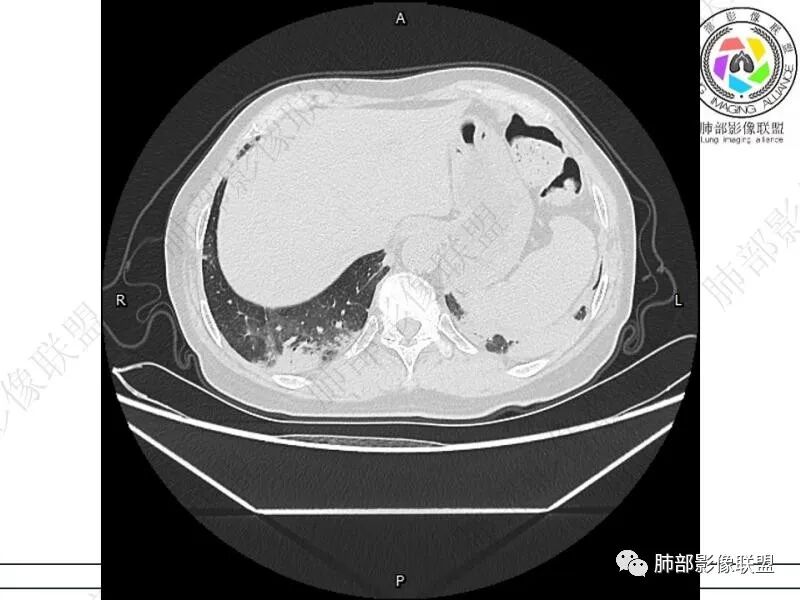

丽:双肺下叶胸膜下多发片状高密度影,边缘模糊不清,内可见支气管穿行,病变长轴平行于胸膜,考虑感染性病变,隐球菌

谢加平:结肠癌术后史,两肺胸膜下多发结节及斑块实变病灶,实边边界平直征(亚急性和慢性病变过程),双肺下叶后基底段胸膜下为甚,与胸膜平行特点,见支气管充气征,边缘模糊的GG0,首诊2022年11月18日肺部CT,与治疗11月28日对比,病灶未吸收,双肺下叶胸膜下病灶有侧向融合特点,综合分析符合炎性肉芽肿,隐球菌感染。

老年女性,结肠癌术后。两下肺胸膜下为主片状实变,右下肺短期复查融合且病灶长轴平行于胸膜,实变内可见支气管充气征,边缘磨玻璃晕,另两肺内胸膜下散在数枚小结节状、楔形实性灶。考虑感染性病变,隐球菌可能,鉴别肺转移。

THINKER:胸膜下实变,常见OP丶PC丶PE丶腺癌丶腺病毒丶非典型病原体。1.此例肠癌,免疫妥协人群,PC要考虑,但荚膜抗原阴性,阴性预测值很高。2.肿瘤史,本身易高凝状态,肺栓塞要考虑。3.OP  胸膜下实变,经典型OP影像。故:PE>OP>PC

2.影像特征:双肺胸膜下多发实性结节、磨玻璃影及实变影,胸膜下优势分布、晕征、胸膜下脂肪间隙存在,部分病灶边界平直征,有侧向融合趋势。